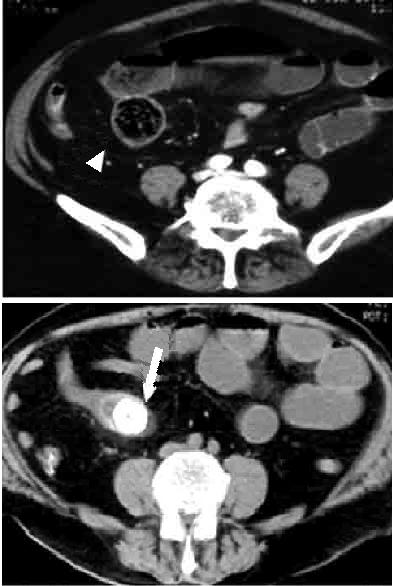

| Hernie inguinale etranglee : Image TDM en

coupe axiale a travers L5 |

Hernie

inguinale etranglee : Meme cas en coupe axiale a

travers symphyse pulbienne |

| Hernie inguinale etrangle : Image

d'engage du grele dans fossette inguinale

moyenne + image de distension de l'intestin au

dessus de l'obstacle ( fleche rouge ) . |

La TDM est tres

l'interet de presiser facilement le type de hernie :

hernie inguinale direct etrangle avec image de grele

en de dans des vaisseaux epigastriques .La TDM peut

differentiele avec les autres masses de la region

scrotale . |